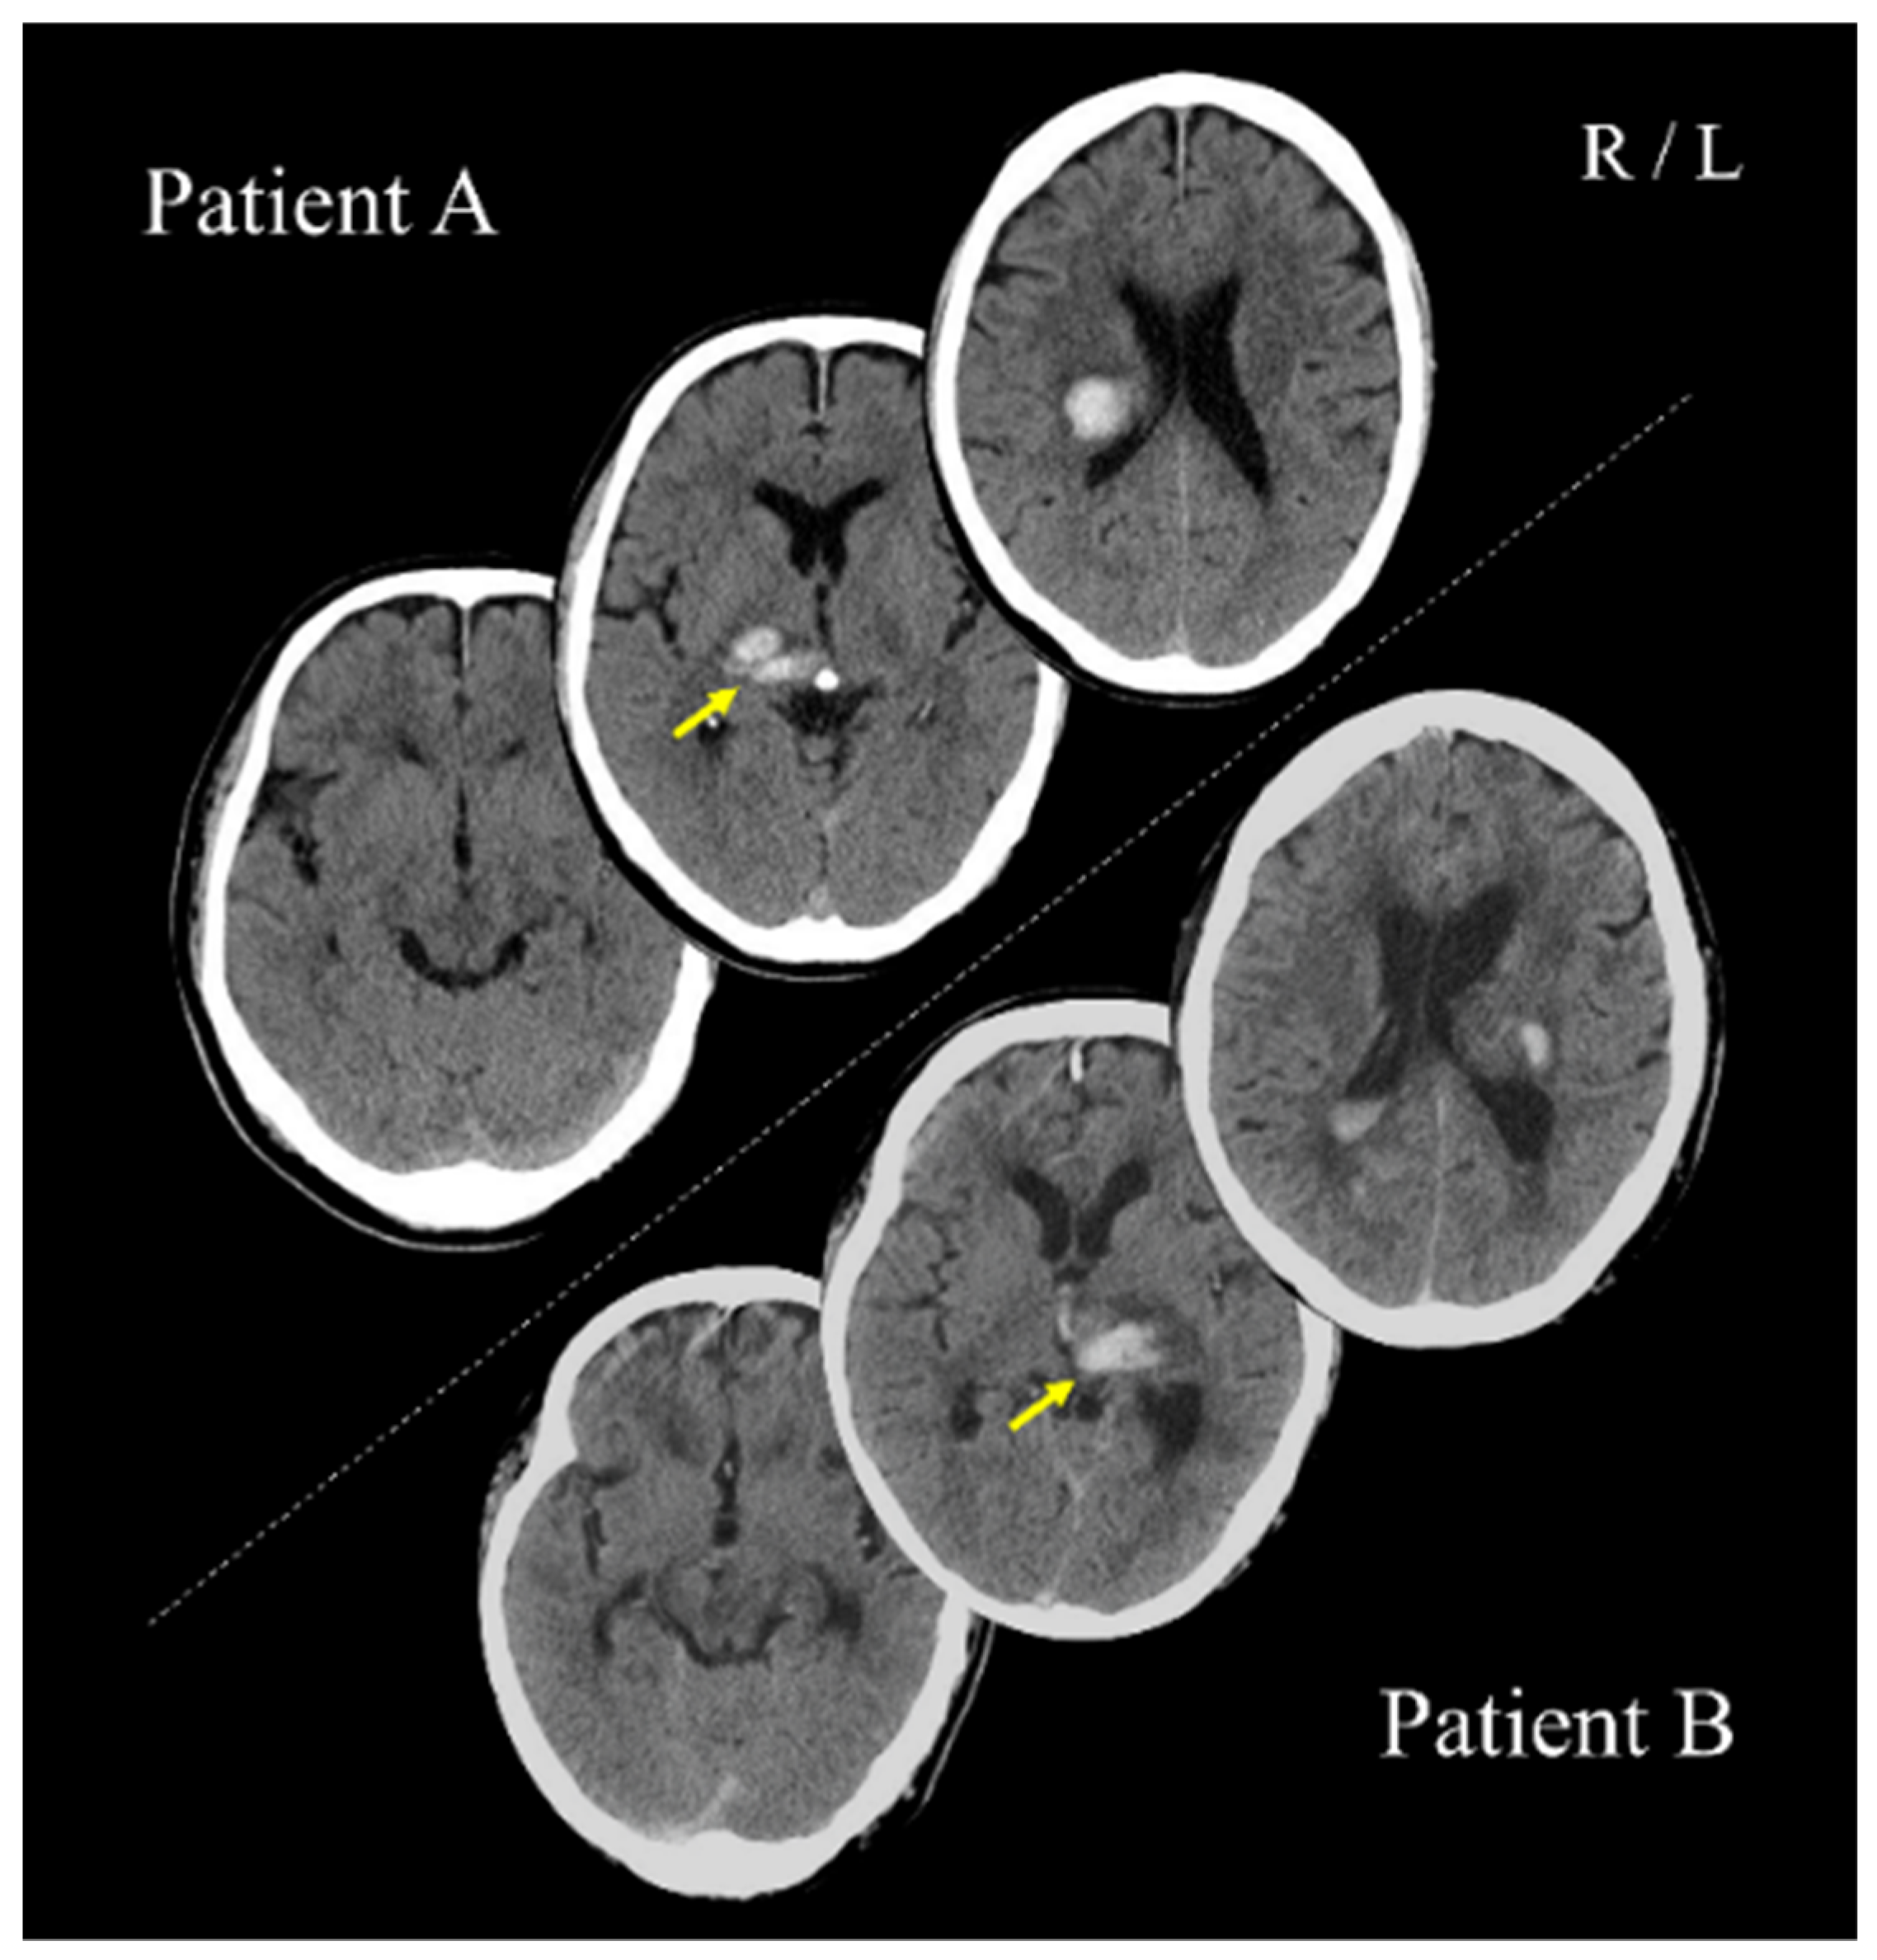

Patients A (PA; 70s; male) and B (PB; 60s; male) with post-stroke upper limb sensorimotor deficits, as well as three healthy adults (27–30 years; two women), participated in the study. PA and PB had right and left thalamic hemorrhage strokes, respectively (Figure 1). For PA and PB, 64 and 67 days had passed since stroke onset, respectively. All participants were right-handed. This study was conducted with the approval of the Ethics Committee of the Jinjukai Ishikawa Hospital (2018-1). All participants provided written informed consent.

Figure 1. Computed tomography scans show the lesion sites of patients A and B. These images were acquired within a day after stroke onset. Yellow arrows indicate the lesion sites. R: right hemisphere; L: left hemisphere.